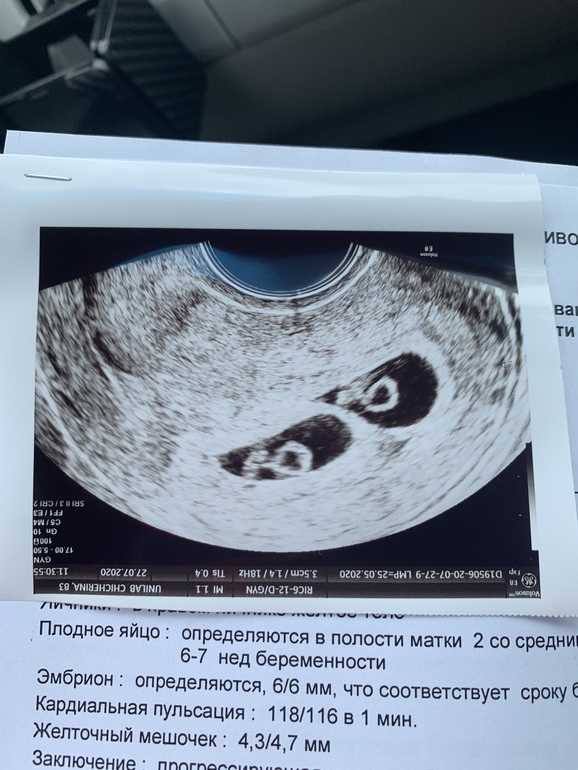

Прикрепляю фото на память) наше второе узи с эбриончиками